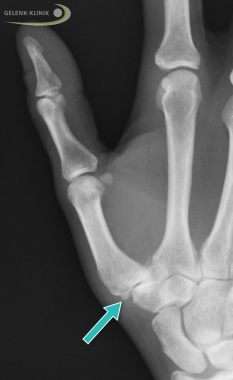

Röntgenbild einer Rhizarthrose: Sichtbar sind die knöchernen Anbauten im Gelenk (Osteophyten, Pfeil) und der deutlich verschmälerte Gelenkspalt. © Gelenk-Klinik

Sklerotische Veränderungen (Verknöcherungen) des Daumengelenks und Osteophyten (Knochenanbauten) an der Gelenkfläche stellt der Orthopäde durch Tasten (Palpation) fest. Fehlstellungen und Konturveränderungen des Daumensattelgelenks sieht er durch äußerliche Betrachtung.